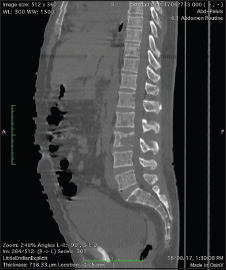

Serum-free kappa light chain was normal, but serum-free lambda was 25.1 mg/dl (elevated) with altered free kappa lambda ratio. Beta-2 macroglobulin was 5.57 which was elevated indicating stage 3 of the disease. In view of right-sided basal crepitations, computed tomography (CT) of the thorax was done, which showed bilateral lower lobe lung parenchymal opacities with pleural effusion and multiple lytic lesions in the spine. As the spleen was just palpable with diffuse tenderness, CT of the abdomen was done which showed thickening with air density pockets in the right psoas and iliacus muscle and splenomegaly and multiple lytic lesions in the vertebral column with pathological fractures [Figure 2], [Figure 3], [Figure 4], [Figure 5]. As this patient also had significant skin manifestations, suspicion toward osteosclerotic myeloma/Crow-Fukase syndrome was made. Hence, the patient was worked up [Figure 6].

| Figure. 3 Computed tomography abdomen showing organomegaly with multiple lytic lesions over the spine

| Figure. 4 Computed tomography of the abdomen showing splenomegaly

| Figure. 5 Computed tomography of the abdomen showed thickening with air density pockets in the right psoas and iliacus muscle and splenomegaly and multiple lytic lesions in the vertebral column with pathological fractures